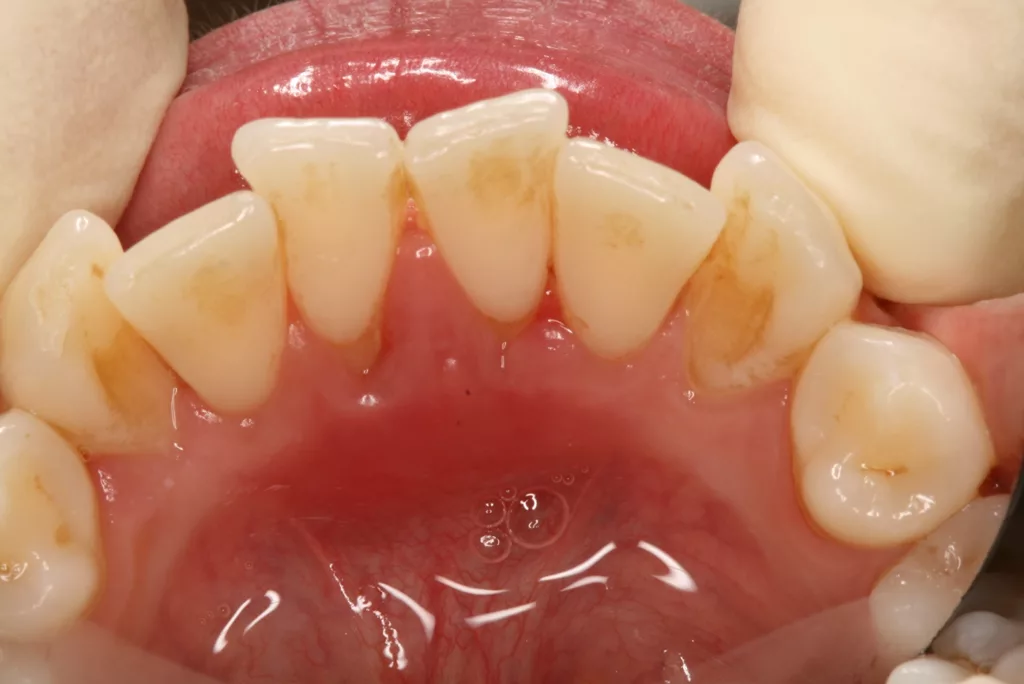

Wir sind vor mittlerweile 17 Jahren erstmals mit der Frage etwaiger Auswirkungen oraler Piercings auf den Zahnhalteapparat konfrontiert worden [10]. Eine damals 24-jährige Patientin stellte sich mit einem ungewöhnlichen Befund vor (Abb. 3a bis d). Bei sonst parodontal unauffälligen Verhältnissen mit Sondierungstiefen zwischen 2 und 3 mm, reichten die Sondierungstiefen an den Schneidezähnen im Unterkiefer bis 12 mm. Zahn 41 schmerzte und wies eine erhöhte Lockerung von Grad 2 auf. Bukkal war zudem eine Fistel mit Pusentleerung zu detektieren. Die Patientin war allgemeinmedizinisch gesund, rauchte nicht und hatte auch keinen Diabetes mellitus. Eine familiäre Prädisposition für parodontale Erkrankungen ließ sich anamnestisch nicht konstruieren. Die Mundhygiene war zwar nicht perfekt, stand aber auch in keinem Verhältnis zu ihrem dramatischen lokalen parodontalen Befund. Im Rahmen der anamnestischen Befragung, fokussiert auf ungewöhnliche Habits, berichtete die Patientin, bis vor kurzem ein Zungenpiercing getragen zu haben, dieses aber vor ca. sechs Monaten entfernt zu haben. Die Piercing-Tragedauer betrug etwa drei Jahre.

![Abb. 3a: Klinische Dokumentation einer 24-jährigen Patientin mit einer weit fortgeschrittenen lokalen parodontalen Destruktion, die mit großer Wahrscheinlichkeit durch ein Zungenpiercing hervorgerufen wurde [10]. Mit Ausnahme der Symptomatik im Unterkiefer-Frontzahnbereich wies die Patientin flache Sondierungstiefen und einzelne Regionen mit Gingivitis auf. Die Zähne reagierten positiv auf eine Sensibilitätsprobe mit Kältespray. Das Piercing war zum Zeitpunkt der Vorstellung in der Klinik bereits nicht mehr im Mund. Es wurde eine stufenweise systematische parodontale Therapie eingeleitet. Die verbliebenen und nahezu unveränderten erhöhten Son¬dierungstiefen wurden einem parodontal-chirurgischen Eingriff mit zusätzlichen, die Regenera¬tion fördernden Maßnahmen (Straumann Emdogain, Straumann, Basel, Schweiz) unterzogen. Es wurde die für diese Operationen empfohlene Schnittführung im Sinne eines Papillenerhaltungs¬lappens angewendet. Der nach der Degranulierung mit Hand- und Ultraschallinstrumenten sicht¬bare knöcherne Defekt wies eine ungünstige Morphologie für die Regeneration auf. Ein primärer Wundverschluss wurde dennoch erzielt. Diese Ansätze blieben letztendlich erfolglos und der Zahn 41 ging verloren (parodontologische Therapie gemeinsam mit Dr. L. Büttel, Basel, Schweiz).](https://dentalwelt.spitta.de/wp-content/uploads/2025/07/Abb-3a-1024x684.webp)

![Abb. 3b: Klinische Dokumentation einer 24-jährigen Patientin mit einer weit fortgeschrittenen lokalen parodontalen Destruktion, die mit großer Wahrscheinlichkeit durch ein Zungenpiercing hervorgerufen wurde [10]. Mit Ausnahme der Symptomatik im Unterkiefer-Frontzahnbereich wies die Patientin flache Sondierungstiefen und einzelne Regionen mit Gingivitis auf. Die Zähne reagierten positiv auf eine Sensibilitätsprobe mit Kältespray. Das Piercing war zum Zeitpunkt der Vorstellung in der Klinik bereits nicht mehr im Mund. Es wurde eine stufenweise systematische parodontale Therapie eingeleitet. Die verbliebenen und nahezu unveränderten erhöhten Son¬dierungstiefen wurden einem parodontal-chirurgischen Eingriff mit zusätzlichen, die Regenera¬tion fördernden Maßnahmen (Straumann Emdogain, Straumann, Basel, Schweiz) unterzogen. Es wurde die für diese Operationen empfohlene Schnittführung im Sinne eines Papillenerhaltungs¬lappens angewendet. Der nach der Degranulierung mit Hand- und Ultraschallinstrumenten sicht¬bare knöcherne Defekt wies eine ungünstige Morphologie für die Regeneration auf. Ein primärer Wundverschluss wurde dennoch erzielt. Diese Ansätze blieben letztendlich erfolglos und der Zahn 41 ging verloren (parodontologische Therapie gemeinsam mit Dr. L. Büttel, Basel, Schweiz).](https://dentalwelt.spitta.de/wp-content/uploads/2025/07/Abb-3b-1024x684.webp)

![Abb. 3c: Klinische Dokumentation einer 24-jährigen Patientin mit einer weit fortgeschrittenen lokalen parodontalen Destruktion, die mit großer Wahrscheinlichkeit durch ein Zungenpiercing hervorgerufen wurde [10]. Mit Ausnahme der Symptomatik im Unterkiefer-Frontzahnbereich wies die Patientin flache Sondierungstiefen und einzelne Regionen mit Gingivitis auf. Die Zähne reagierten positiv auf eine Sensibilitätsprobe mit Kältespray. Das Piercing war zum Zeitpunkt der Vorstellung in der Klinik bereits nicht mehr im Mund. Es wurde eine stufenweise systematische parodontale Therapie eingeleitet. Die verbliebenen und nahezu unveränderten erhöhten Son¬dierungstiefen wurden einem parodontal-chirurgischen Eingriff mit zusätzlichen, die Regenera¬tion fördernden Maßnahmen (Straumann Emdogain, Straumann, Basel, Schweiz) unterzogen. Es wurde die für diese Operationen empfohlene Schnittführung im Sinne eines Papillenerhaltungs¬lappens angewendet. Der nach der Degranulierung mit Hand- und Ultraschallinstrumenten sicht¬bare knöcherne Defekt wies eine ungünstige Morphologie für die Regeneration auf. Ein primärer Wundverschluss wurde dennoch erzielt. Diese Ansätze blieben letztendlich erfolglos und der Zahn 41 ging verloren (parodontologische Therapie gemeinsam mit Dr. L. Büttel, Basel, Schweiz).](https://dentalwelt.spitta.de/wp-content/uploads/2025/07/Abb-3c-1024x722.webp)

![Abb. 3d: Klinische Dokumentation einer 24-jährigen Patientin mit einer weit fortgeschrittenen lokalen parodontalen Destruktion, die mit großer Wahrscheinlichkeit durch ein Zungenpiercing hervorgerufen wurde [10]. Mit Ausnahme der Symptomatik im Unterkiefer-Frontzahnbereich wies die Patientin flache Sondierungstiefen und einzelne Regionen mit Gingivitis auf. Die Zähne reagierten positiv auf eine Sensibilitätsprobe mit Kältespray. Das Piercing war zum Zeitpunkt der Vorstellung in der Klinik bereits nicht mehr im Mund. Es wurde eine stufenweise systematische parodontale Therapie eingeleitet. Die verbliebenen und nahezu unveränderten erhöhten Son¬dierungstiefen wurden einem parodontal-chirurgischen Eingriff mit zusätzlichen, die Regenera¬tion fördernden Maßnahmen (Straumann Emdogain, Straumann, Basel, Schweiz) unterzogen. Es wurde die für diese Operationen empfohlene Schnittführung im Sinne eines Papillenerhaltungs¬lappens angewendet. Der nach der Degranulierung mit Hand- und Ultraschallinstrumenten sicht¬bare knöcherne Defekt wies eine ungünstige Morphologie für die Regeneration auf. Ein primärer Wundverschluss wurde dennoch erzielt. Diese Ansätze blieben letztendlich erfolglos und der Zahn 41 ging verloren (parodontologische Therapie gemeinsam mit Dr. L. Büttel, Basel, Schweiz).](https://dentalwelt.spitta.de/wp-content/uploads/2025/07/Abb-3d-1024x665.webp)